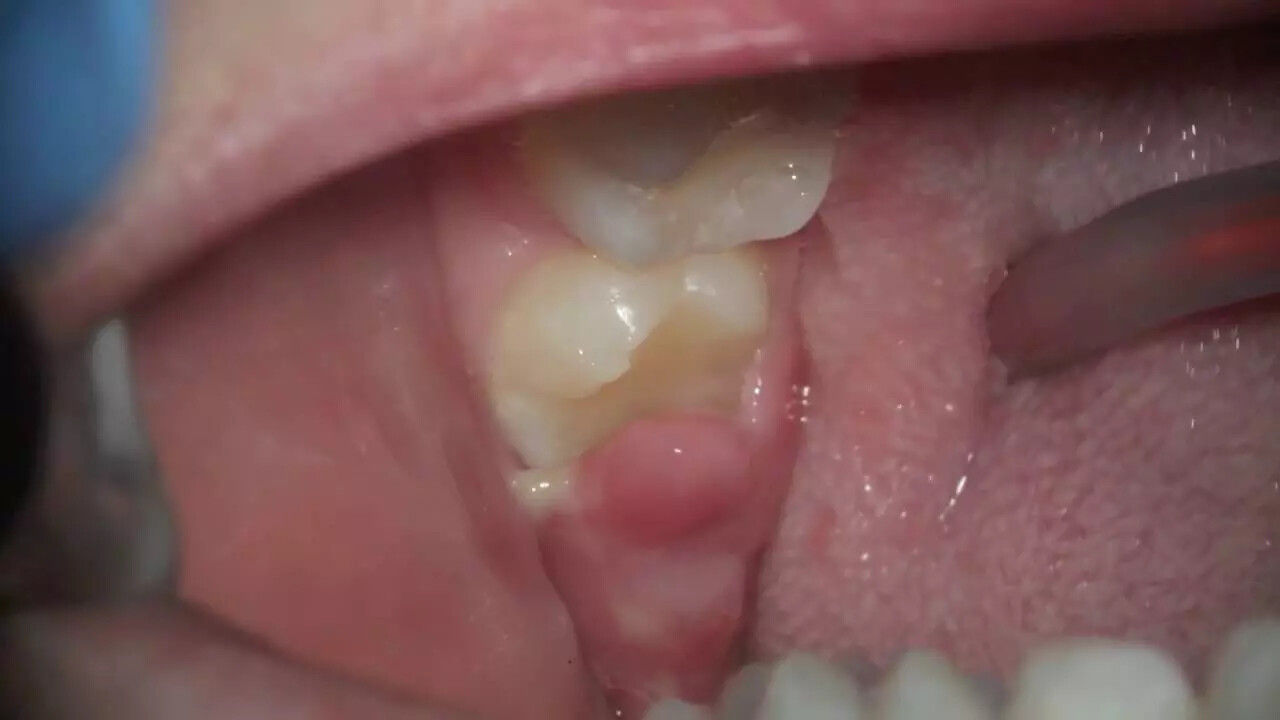

Pericoronitis is the inflammation and infection of tissue surrounding a partially erupted wisdom tooth or teeth, and it’s more common in the lower jaw. Partially impacted molars often have a flap of gum tissue covering the crown of the erupting tooth and this tissue can get food stuck under the gum flap or other debris. This creates a possible breeding ground for bacteria, causing pericoronitis to develop.

Pericoronitis treatment varies because the flap of gum tissue that’s creating the problem won’t go away until the tooth emerges naturally, the tissue is surgically removed, or the tooth is extracted.